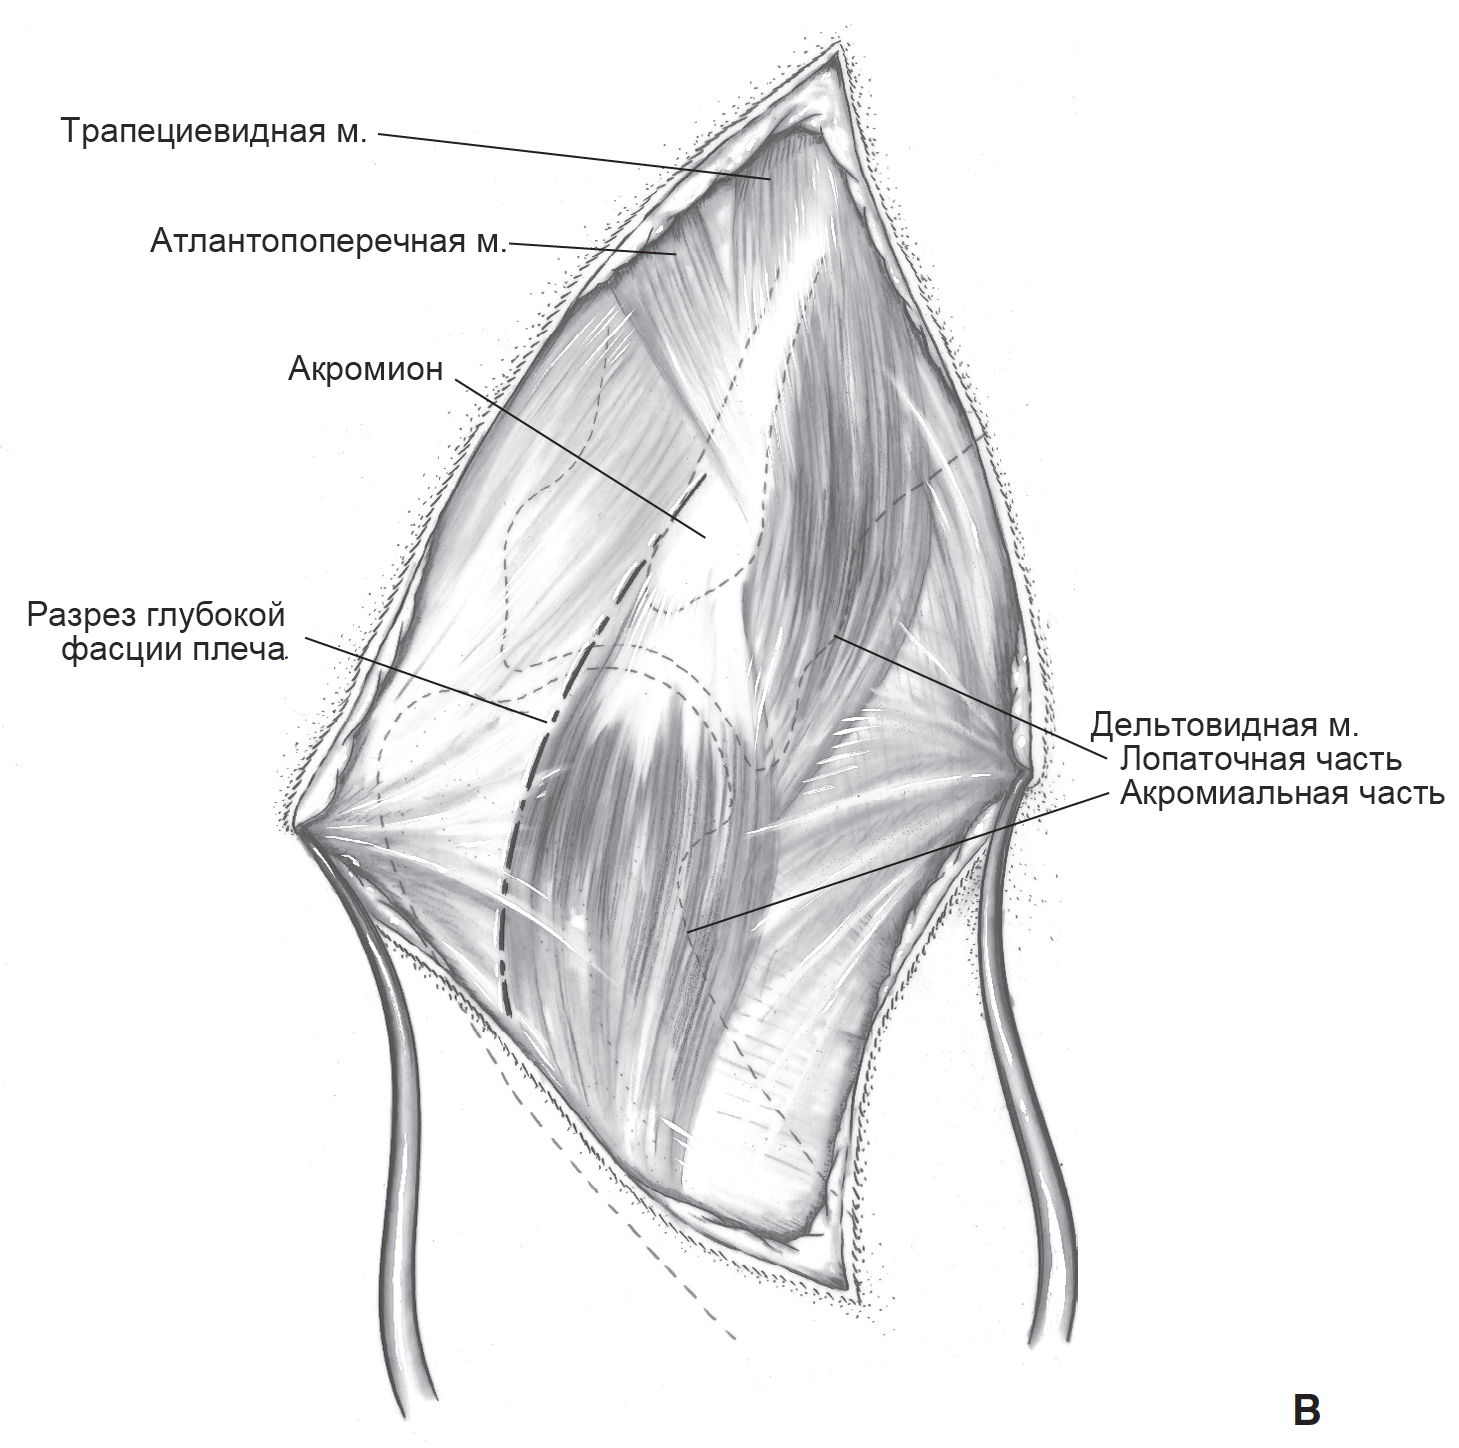

Фотографии поддельтовидной мышцы плечевого сустава